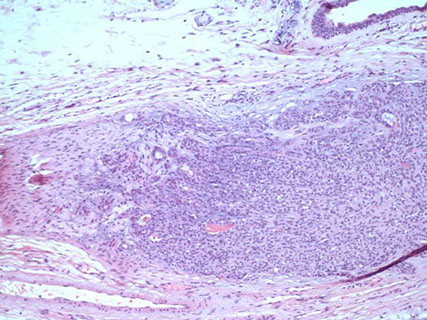

Adenoid Cystic Carcinoma

- aka cylindroma

~1/15 of all salivary gland tumors; seen in older women

- mostly (60%) seen in minor salivary glands, esp in the palate; (MC malignant tumor of minor salivary glands)

Have extensively invasive growth patterns, esp perineural invasion

Micro: Biphasic c ductal lining and ME cells with cribriform, tubular or solid pattern and hyaline material filling the spaces bwt tumors (stromal hyalinization [thick BM])

- usually contains at least some cribriform nests (Swiss cheese) filled c myxoid (blue goo), but may not be present on small bx

- tumor cells should not have intracytoplasmic mucin (found in MEC) - mucin is secreted into pseudocysts - also shound not have squamous metaplasia

- considered high-grade if >30% has solid growth pattern - has calcification / comedonecrosis in high grade

Cytology: carrot-shaped

Genes: LOH at 6q23-35, MYB-NFIB in 1/2

IHC: (+) ME pos for CK (lumen epithelial cells) / p63 (basal-myoepithelial cells) / calponin / SMA / S100 / GFAP, epithelium pos for CK/EMA/CEA/c-kit (luminal) and CD117???

DDx: PLGA (PLGA has less mits, less hyperchromasia, less dense fibrous stroma, smaller nests and less nuclear polymorphism); PA

Tx: Radical excision and rads

Px: Tend to recur and met; thus are high risk and have relatively low 5- and 10-year survivals (MC mets to lung)

- high tendency for perineural invasion

Adenoid cystic ca

High grade adenoid cystic ca c comedo necrosis